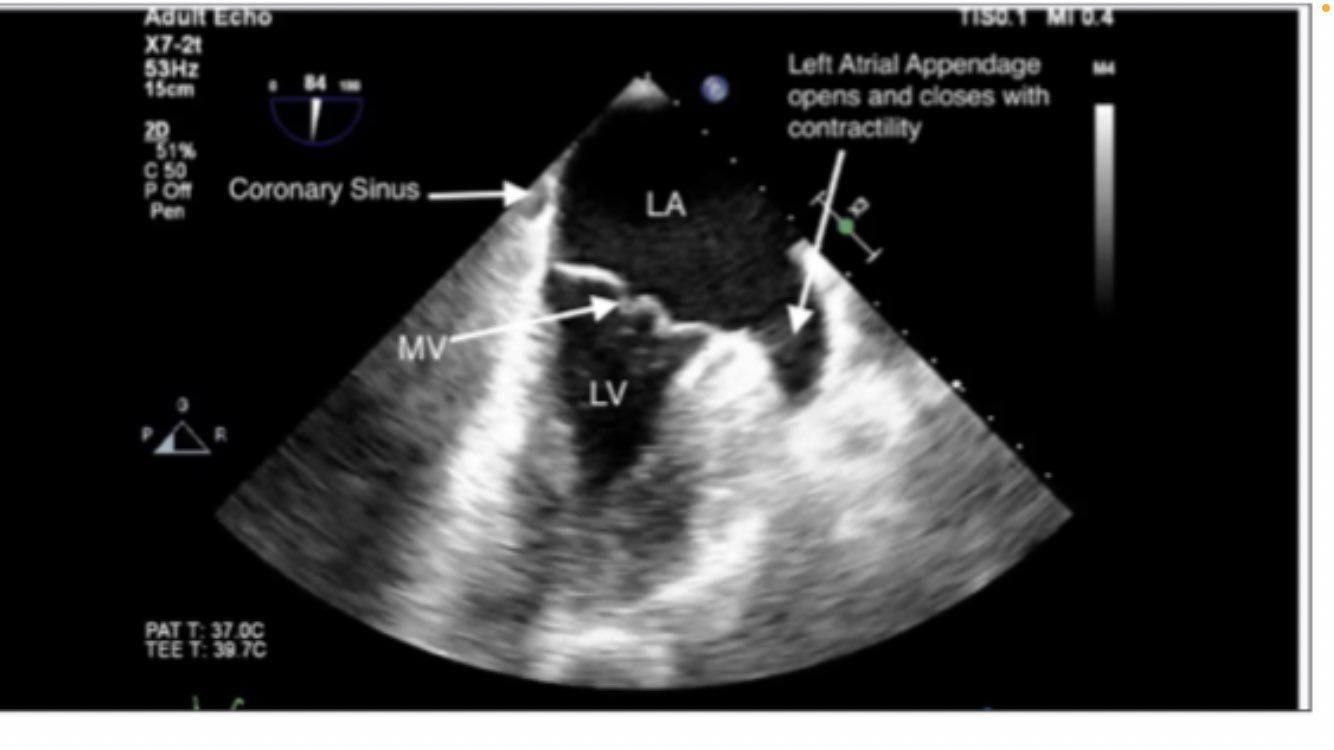

Midesophageal 4 chamber view

midesophageal 4 chamber